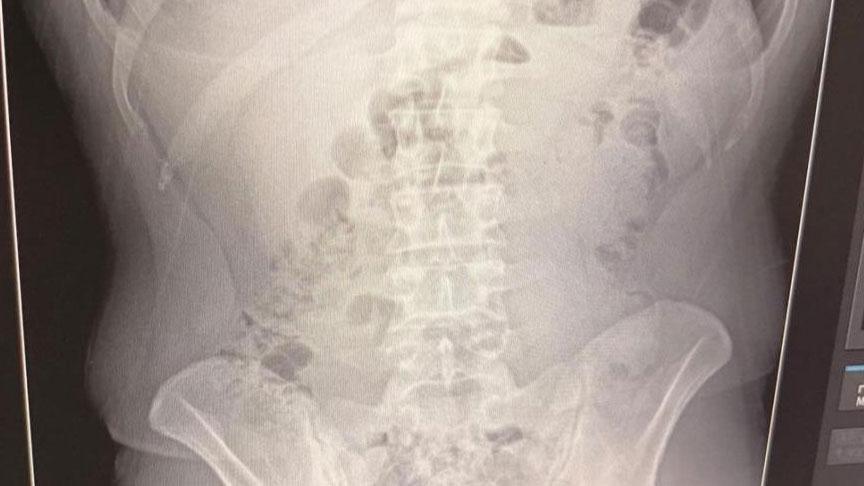

Adreste yapılan arama sırasında ekipler, şüphelilerden birinin üstünde 1 adet kapsül ele geçirdi. Şüphe üzerine tüm şüpheliler hastaneye götürüldü ve yapılan röntgen kontrollerinde 3 kişinin midelerinde kapsül içine gizlenmiş metamfetamin tespit edildi.

Hastanede tedavi altına alınan şüphelilerin vücudundan kapsüller çıkarılırken, adreste ele geçirilenlerle birlikte toplam 1 kilo 516 gram metamfetamin ele geçirildi.